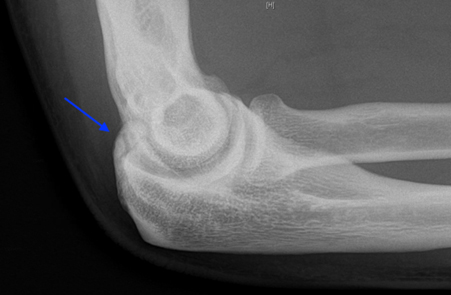

- Radiographs frequently demonstrate osteophyte formation in the posteromedial olecranon

X-ray demonstrating Osteophytes within the olecranon fossa